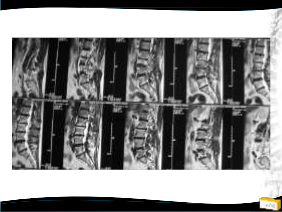

Olgu

• 64y, K

• Bel ve her iki bacak ağrısı

• NM normal

Yapılan Ameliyat: L1-L5 dekompesyon + transpediküler stabilizasyon

• Bel ağrısı, bacaklarında güçsüzlük,

3/5 paraparezi, üriner retansiyon

1. Op: Torakotomiyle T12-L1 diskektomi